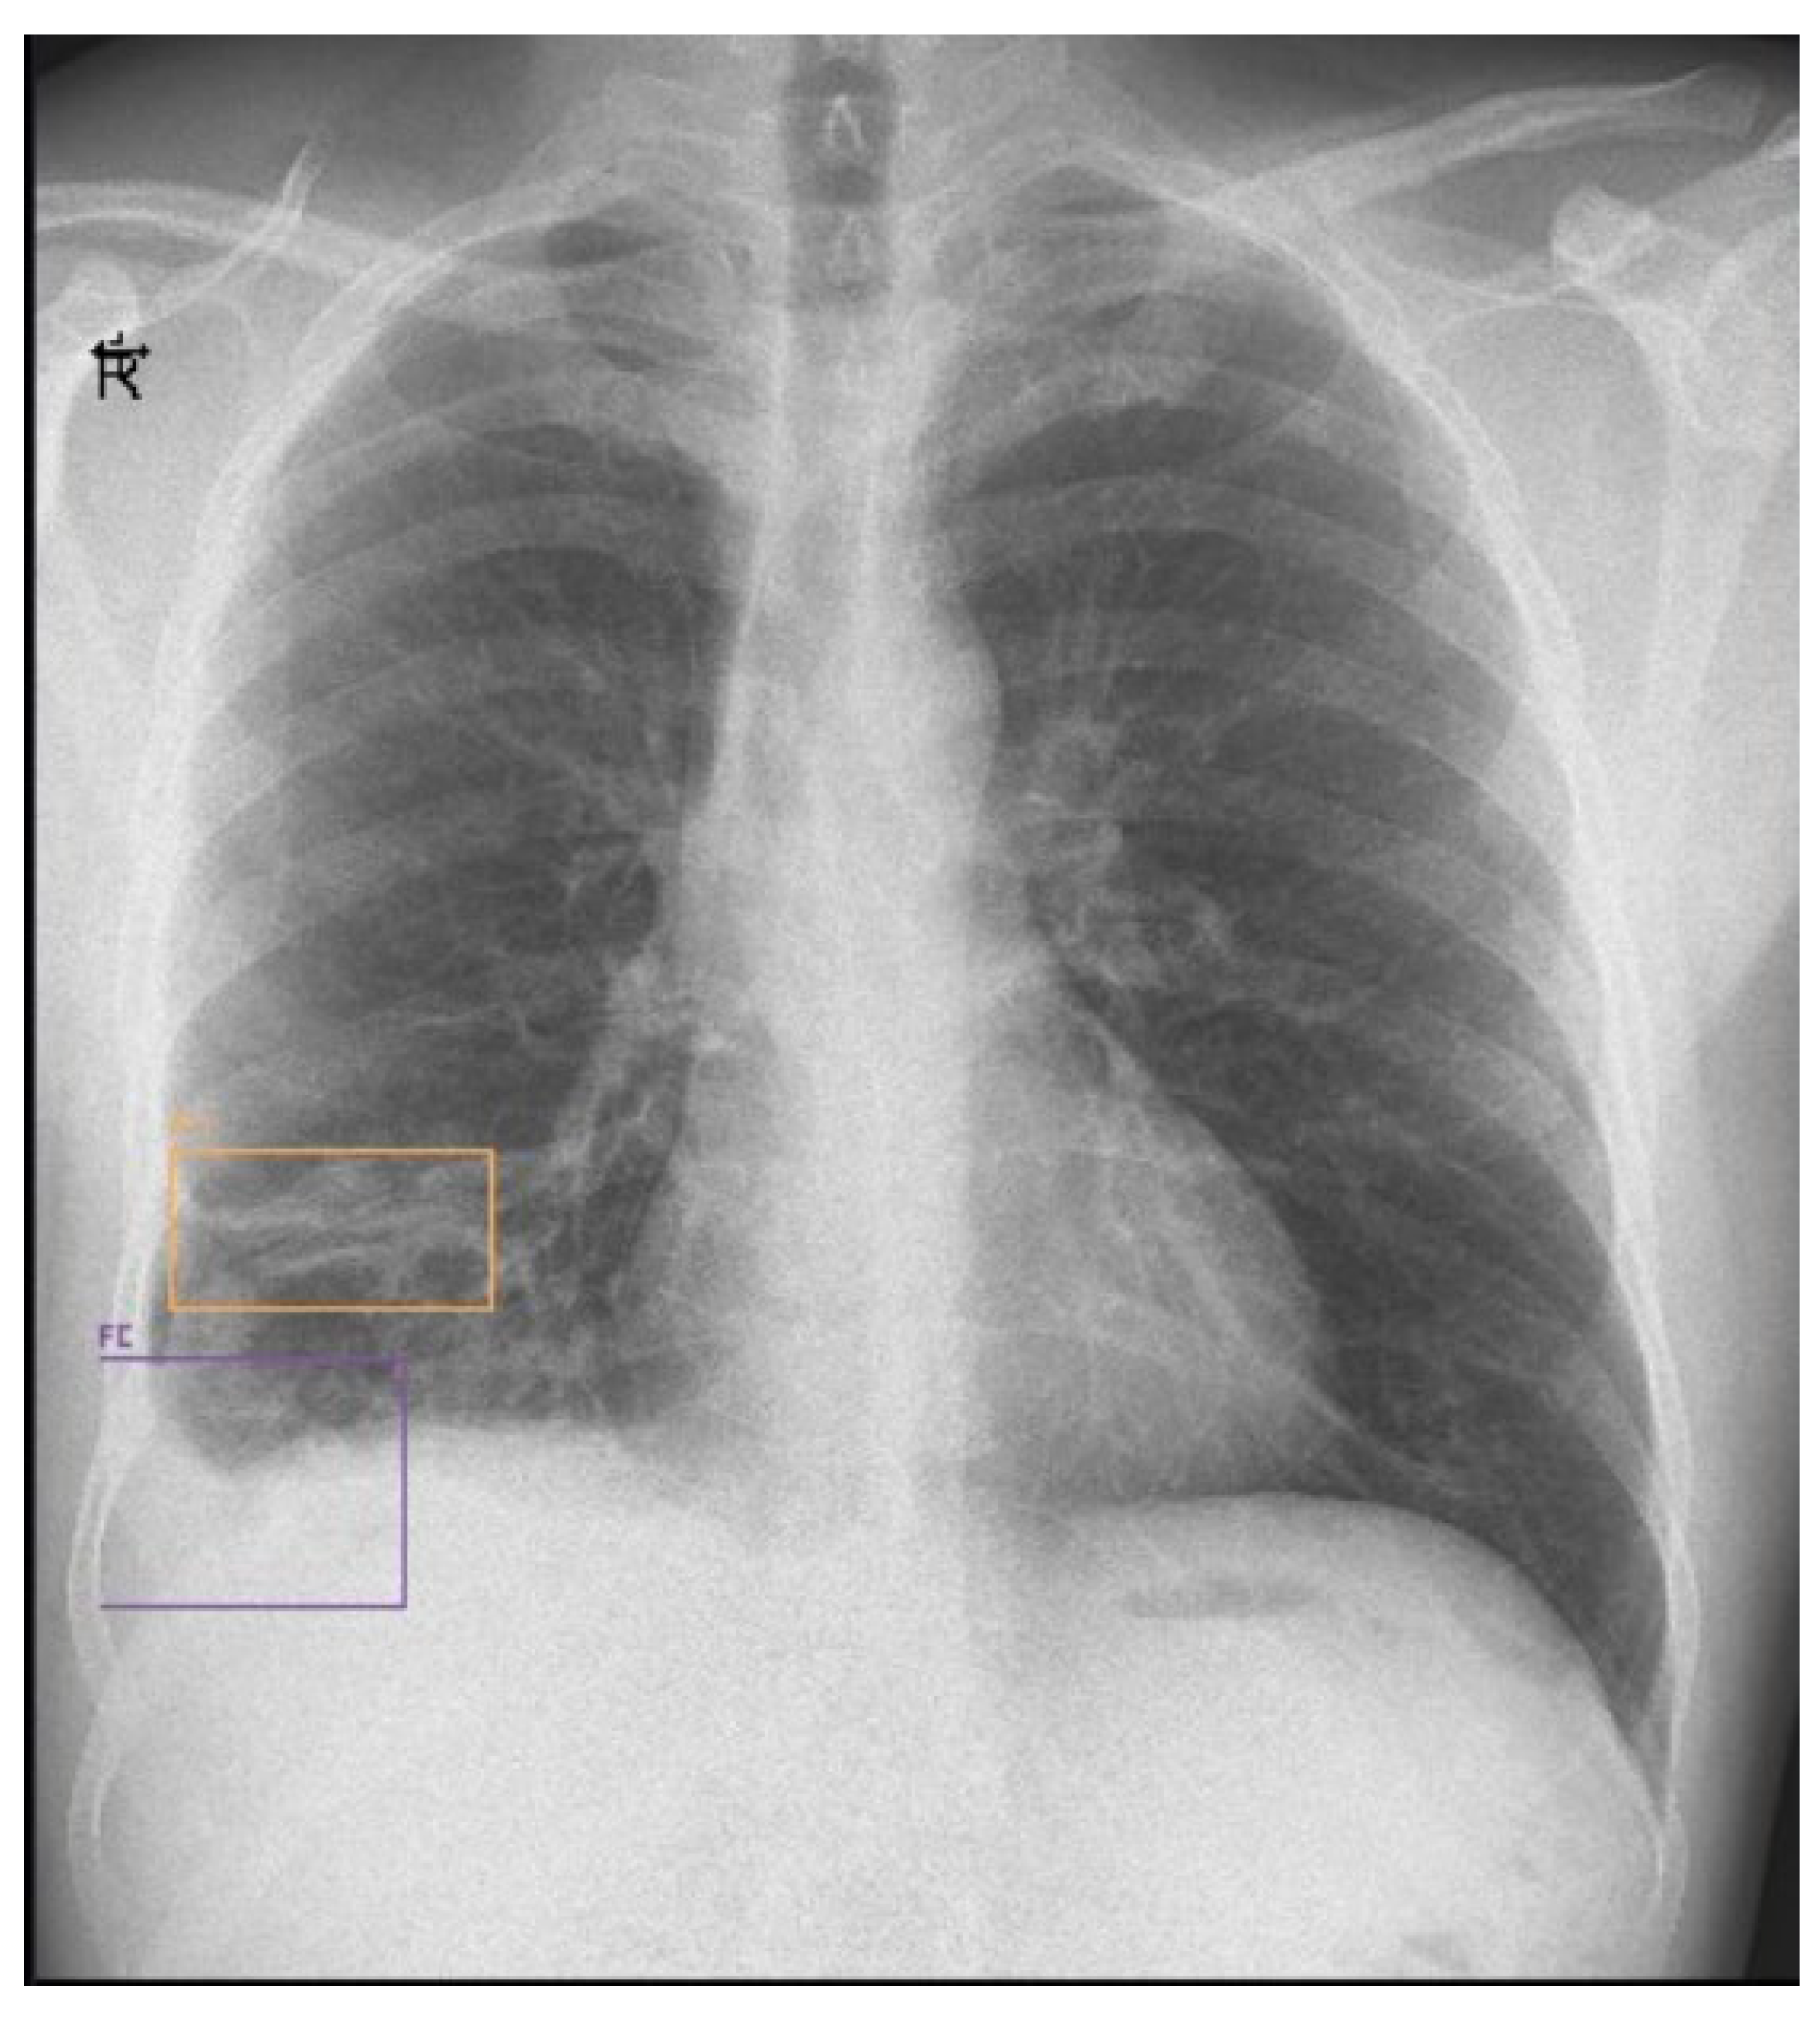

On the twentieth day, the chest X-ray showed multiple hydro-aerial levels up to 85/90 mm on the right lung (Figure 3). A chest computed tomography (CT) revealed free air and fluid levels within the pleural space with collapsed lung parenchyma (hydropneumothorax) and mediastinal lymphadenopaty (Figure 4).

Figure 3. Chest X-ray (day 20) showing hydro-aerial levels.